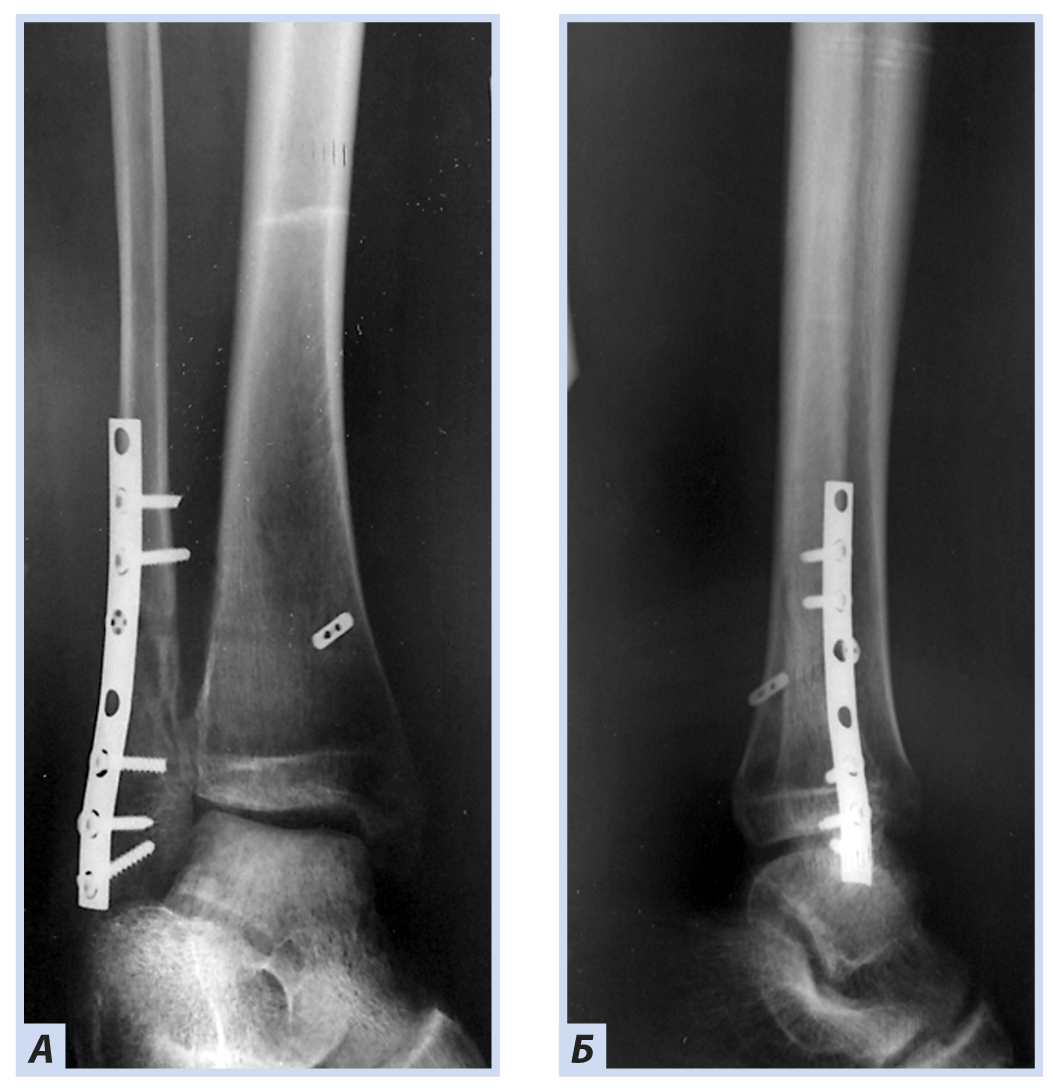

Клиническое наблюдение 3

Мальчик, 16 лет, диагноз «Закрытый перелом обеих лодыжек правого голеностопного сустава с подвывихом стопы кнаружи. Супинационно-эверсионный механизм травмы». Травма получена в результате падения на льду. По данным ультразвуковой диагностики был диагностирован частичный разрыв передней порции дистального межберцового синдесмоза. Выполнен остеосинтез внутренней лодыжки спицами, дистальный межберцовый синдесмоз фиксирован синдесмозной системой (Arthrex Tightrope Ankle), перелом латеральной лодыжки фиксирован 1/3 трубчатой пластиной. Внешняя иммобилизация осуществлена гипсовой лонгетой. Контрольная рентгенография и исследование микроциркуляции в области перелома методом лазерной допплеровской флоуметрии выполнены через 8 нед. после операции. На рентгенограммах имеются признаки зажившего перелома, по данным флоуметрии наблюдается активация капилляризации тканей и нутритивного кровотока в условиях регенераторного процесса. Спицы удалены через 8 нед., конфигурация сустава восстановлена полностью (рис. 10–13).

Рис. 10. Мальчик, 16 лет. Рентгенограммы дистального отдела костей правой голени. Перелом обеих лодыжек правого голеностопного сустава с подвывихом стопы кнаружи: А — прямая проекция; Б — боковая проекция.

Рис. 12. Тот же пациент. Рентгенограммы дистального отдела костей правой голени. Остеосинтез малоберцовой кости пластиной, остеосинтез внутренней лодыжки спицами, фиксация синдесмоза системой Arthrex Tightrope Ankle: А — прямая проекция; Б — боковая проекция.

Рис. 13. Тот же пациент. Рентгенограммы дистального отдела костей правой голени через 8 нед. Консолидация костных отломков: А — прямая проекция; Б — боковая проекция.